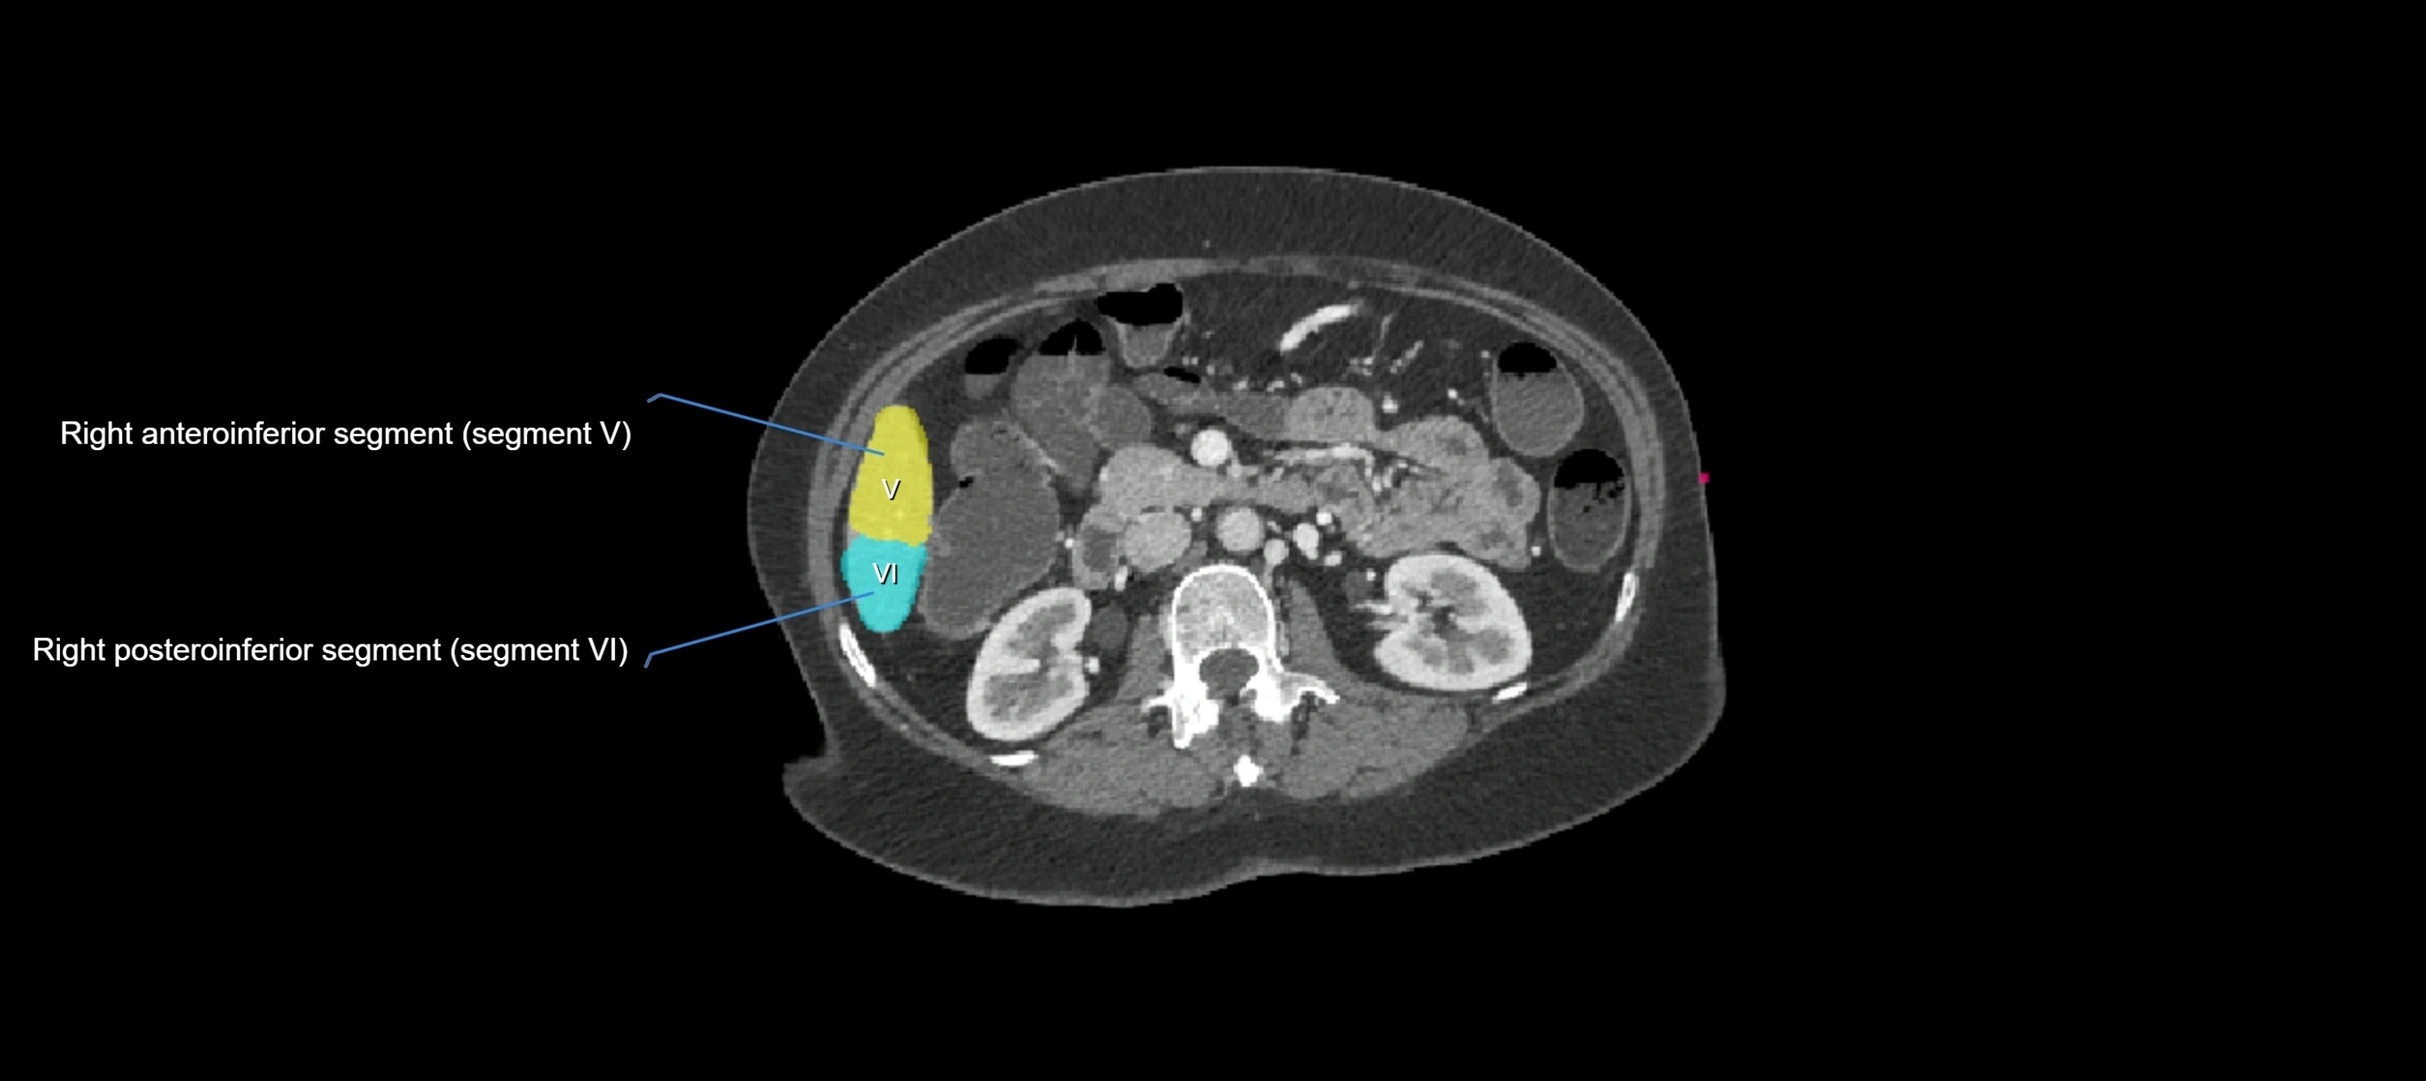

CT Image

image